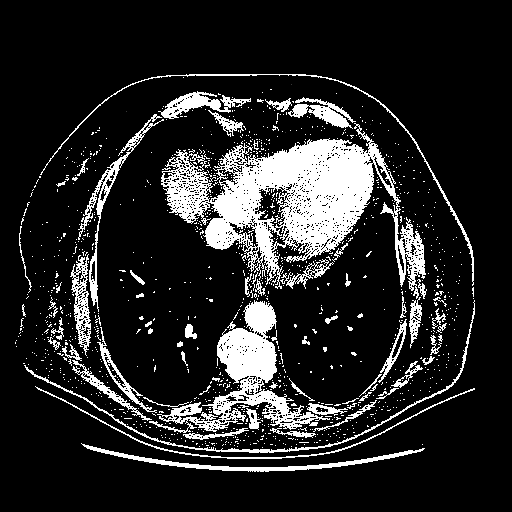

Original NATIVE CT scan (input)

Full window (WL 1023.5, WW 4095 β†’ Low βˆ’1024, High +3071)

Actual HU range: [-1024.0, 3071.0]